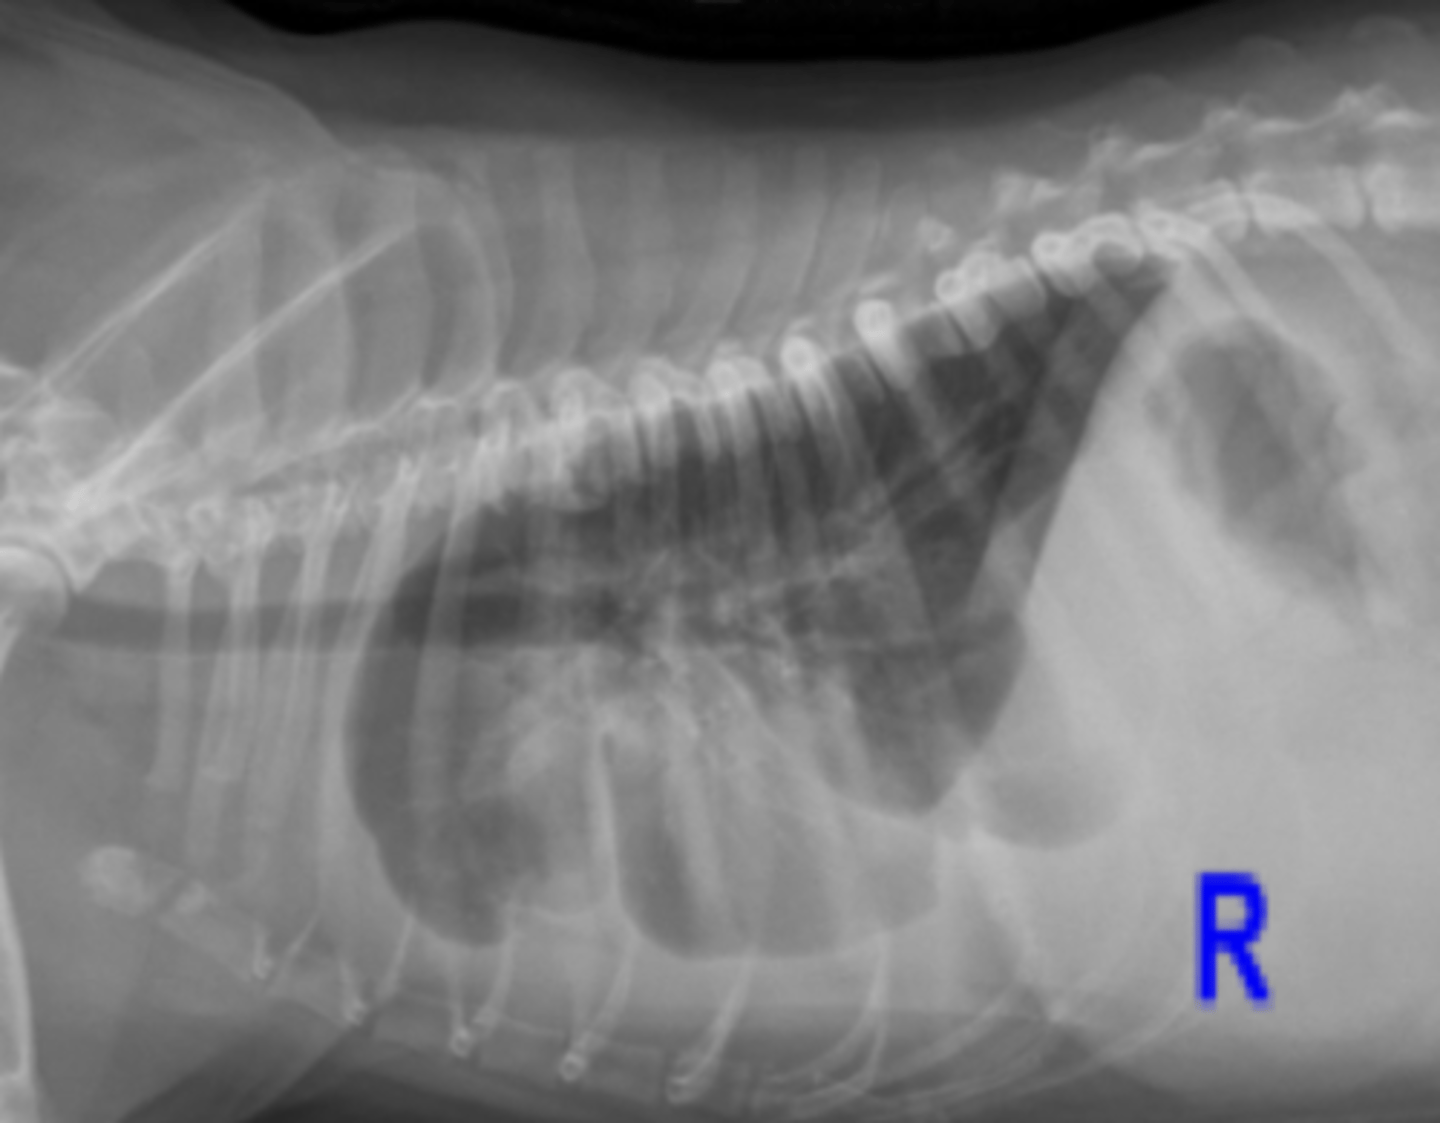

pneumotorax

patología:

patolgía